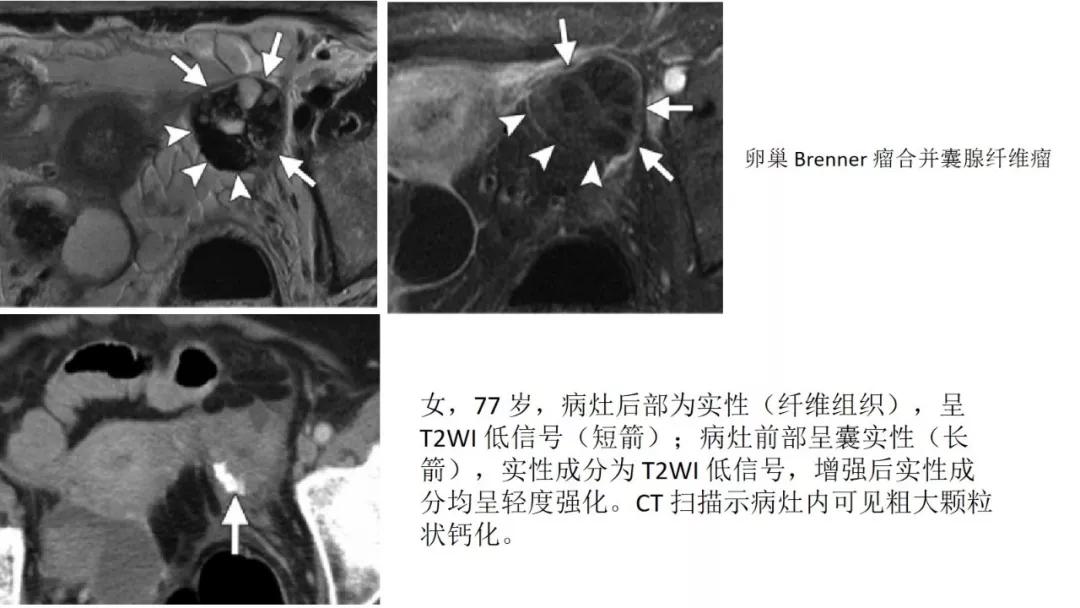

出现钙化:浆液性肿瘤、卵泡膜纤维瘤、畸胎瘤、Brenner瘤